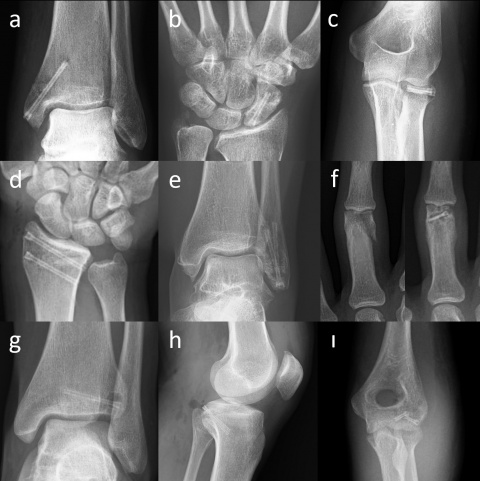

1. Einleitung

Magnesium-Kompressionsschrauben. (a) Mediale Spunggelenksfraktur

(b) Kahnbeinfraktur (c) Radiuskopffraktur (d) Distale Radiusfraktur (e)

Laterale Spunggelenksfraktur (f) Fingerfraktur (g) Tillaux-Fraktur im

Jugendalter (h) Abriss des hinteren Kreuzbands (ı) Capitulum-humeri-

Fraktur

Die Mg-Kompressions-Schraube MAGNEZIX® CS kann für eine ganze Reihe unterschiedlicher Indikationen in der orthopädischen und der Trauma-Chirurgie eingesetzt werden (Abbildung 1): grundsätzlich ist sie geeignet für die Versorgung von Frakturen und Pseudoarthrosen sowie Arthrodesen kleiner Knochen, im Speziellen Kahnbeinfrakturen, Abrissfrakturen, Sprunggelenksfrakturen, intraartikuläre Frakturen der Fußwurzel- und der Mittelfußknochen, der Handwurzel- und Mittelhandknochen, Bunionektomien und Osteotomien am Fuß oder Knöchel, Arthrodesen kleiner Gelenke (z. B. Phalangen), Patella-Frakturen, distale Ulna- und Radiusfrakturen, Radiuskopffrakturen und intraartikuläre Frakturen des distalen Humerus [13].